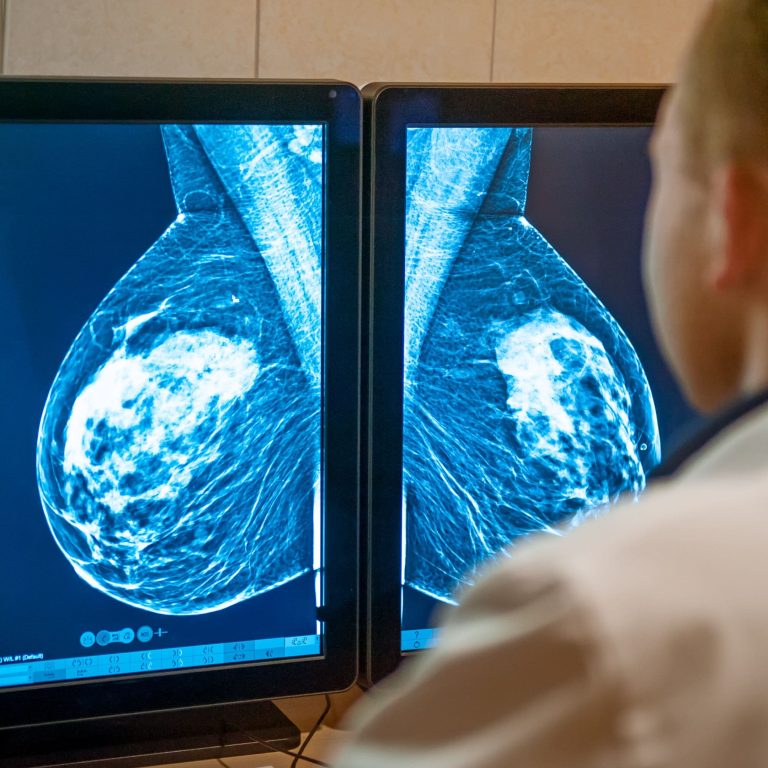

A breast biopsy in Singapore is a medical procedure that extracts a small tissue sample from the breast …

A breast biopsy is a minimally invasive procedure used to obtain a tissue sample from a suspected lump, …